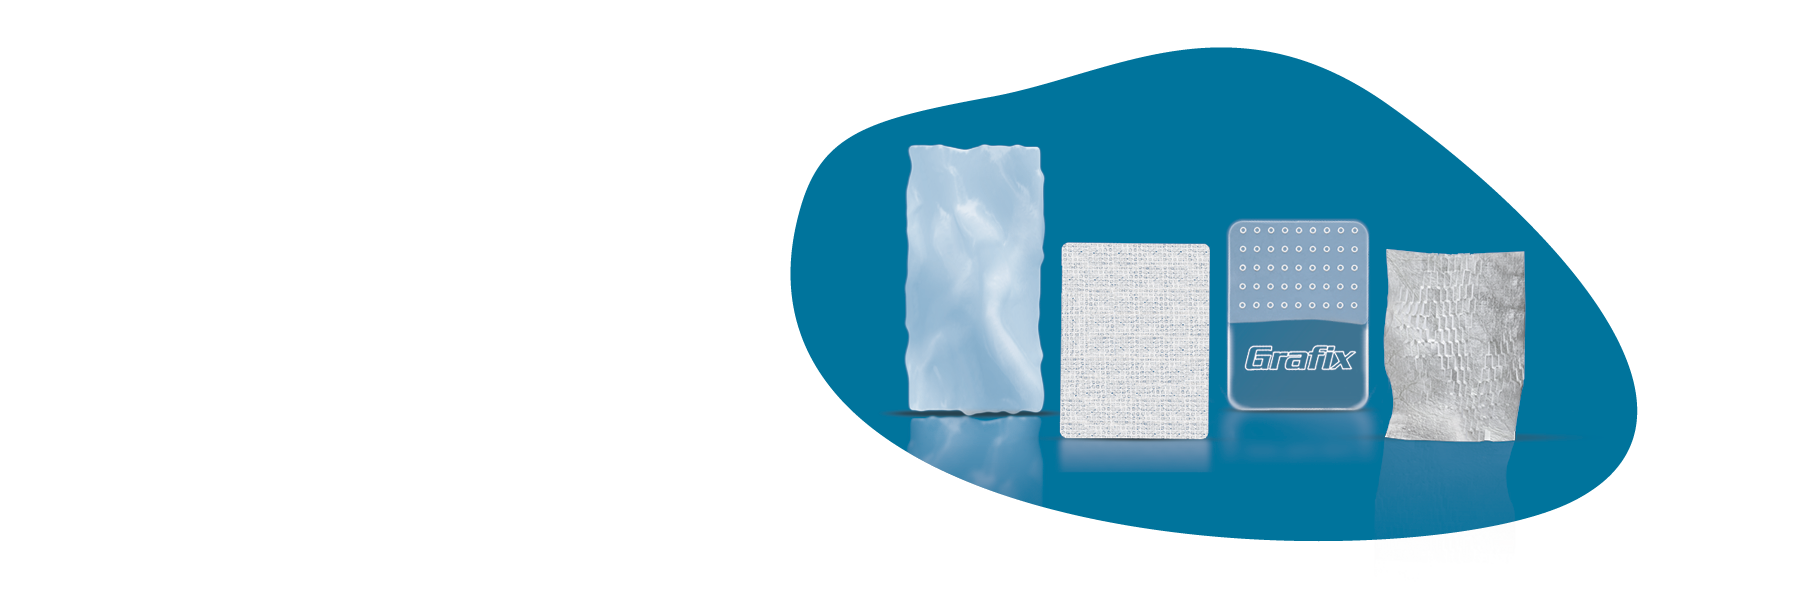

STRAVIX◊ Tissue

Cryopreserved Umbilical Tissue

STRAVIX Tissue is a robust, easy-to-handle graft that sutures easily, conforms intimately, and performs across specialties*, from podiatric wounds to complex soft tissue reconstruction.1

STRAVIX◊ PL

Lyopreserved Umbilical Tissue

STRAVIX PL Tissue was designed for the realities of today’s OR: fast-paced, high-stakes, and never one-size-fits-all. With high tensile strength2 and easy handling, it’s ideal for both compromised surgical sites and complex soft tissue management.

GRAFIX◊ XC

Cryopreserved Placental Membrane

GRAFIX XC Tissue brings the full power of human placental tissue—native cells and an intact extracellular matrix—directly to the wound bed.3,4

GRAFIX PL◊ XC

Lyopreserved Umbilical Tissue

GRAFIX PL XC Tissue is engineered to retain the native structure and key components of fresh human placental tissue, including an intact extracellular matrix and endogenous cells.4,5

OASIS®

Matrix products

OASIS Matrix products are designed to meet your patients where they are. That means across wound types, severity, and care settings. They are ideal for supporting closure in a variety of wounds and can be used alongside standard care protocols.5,6